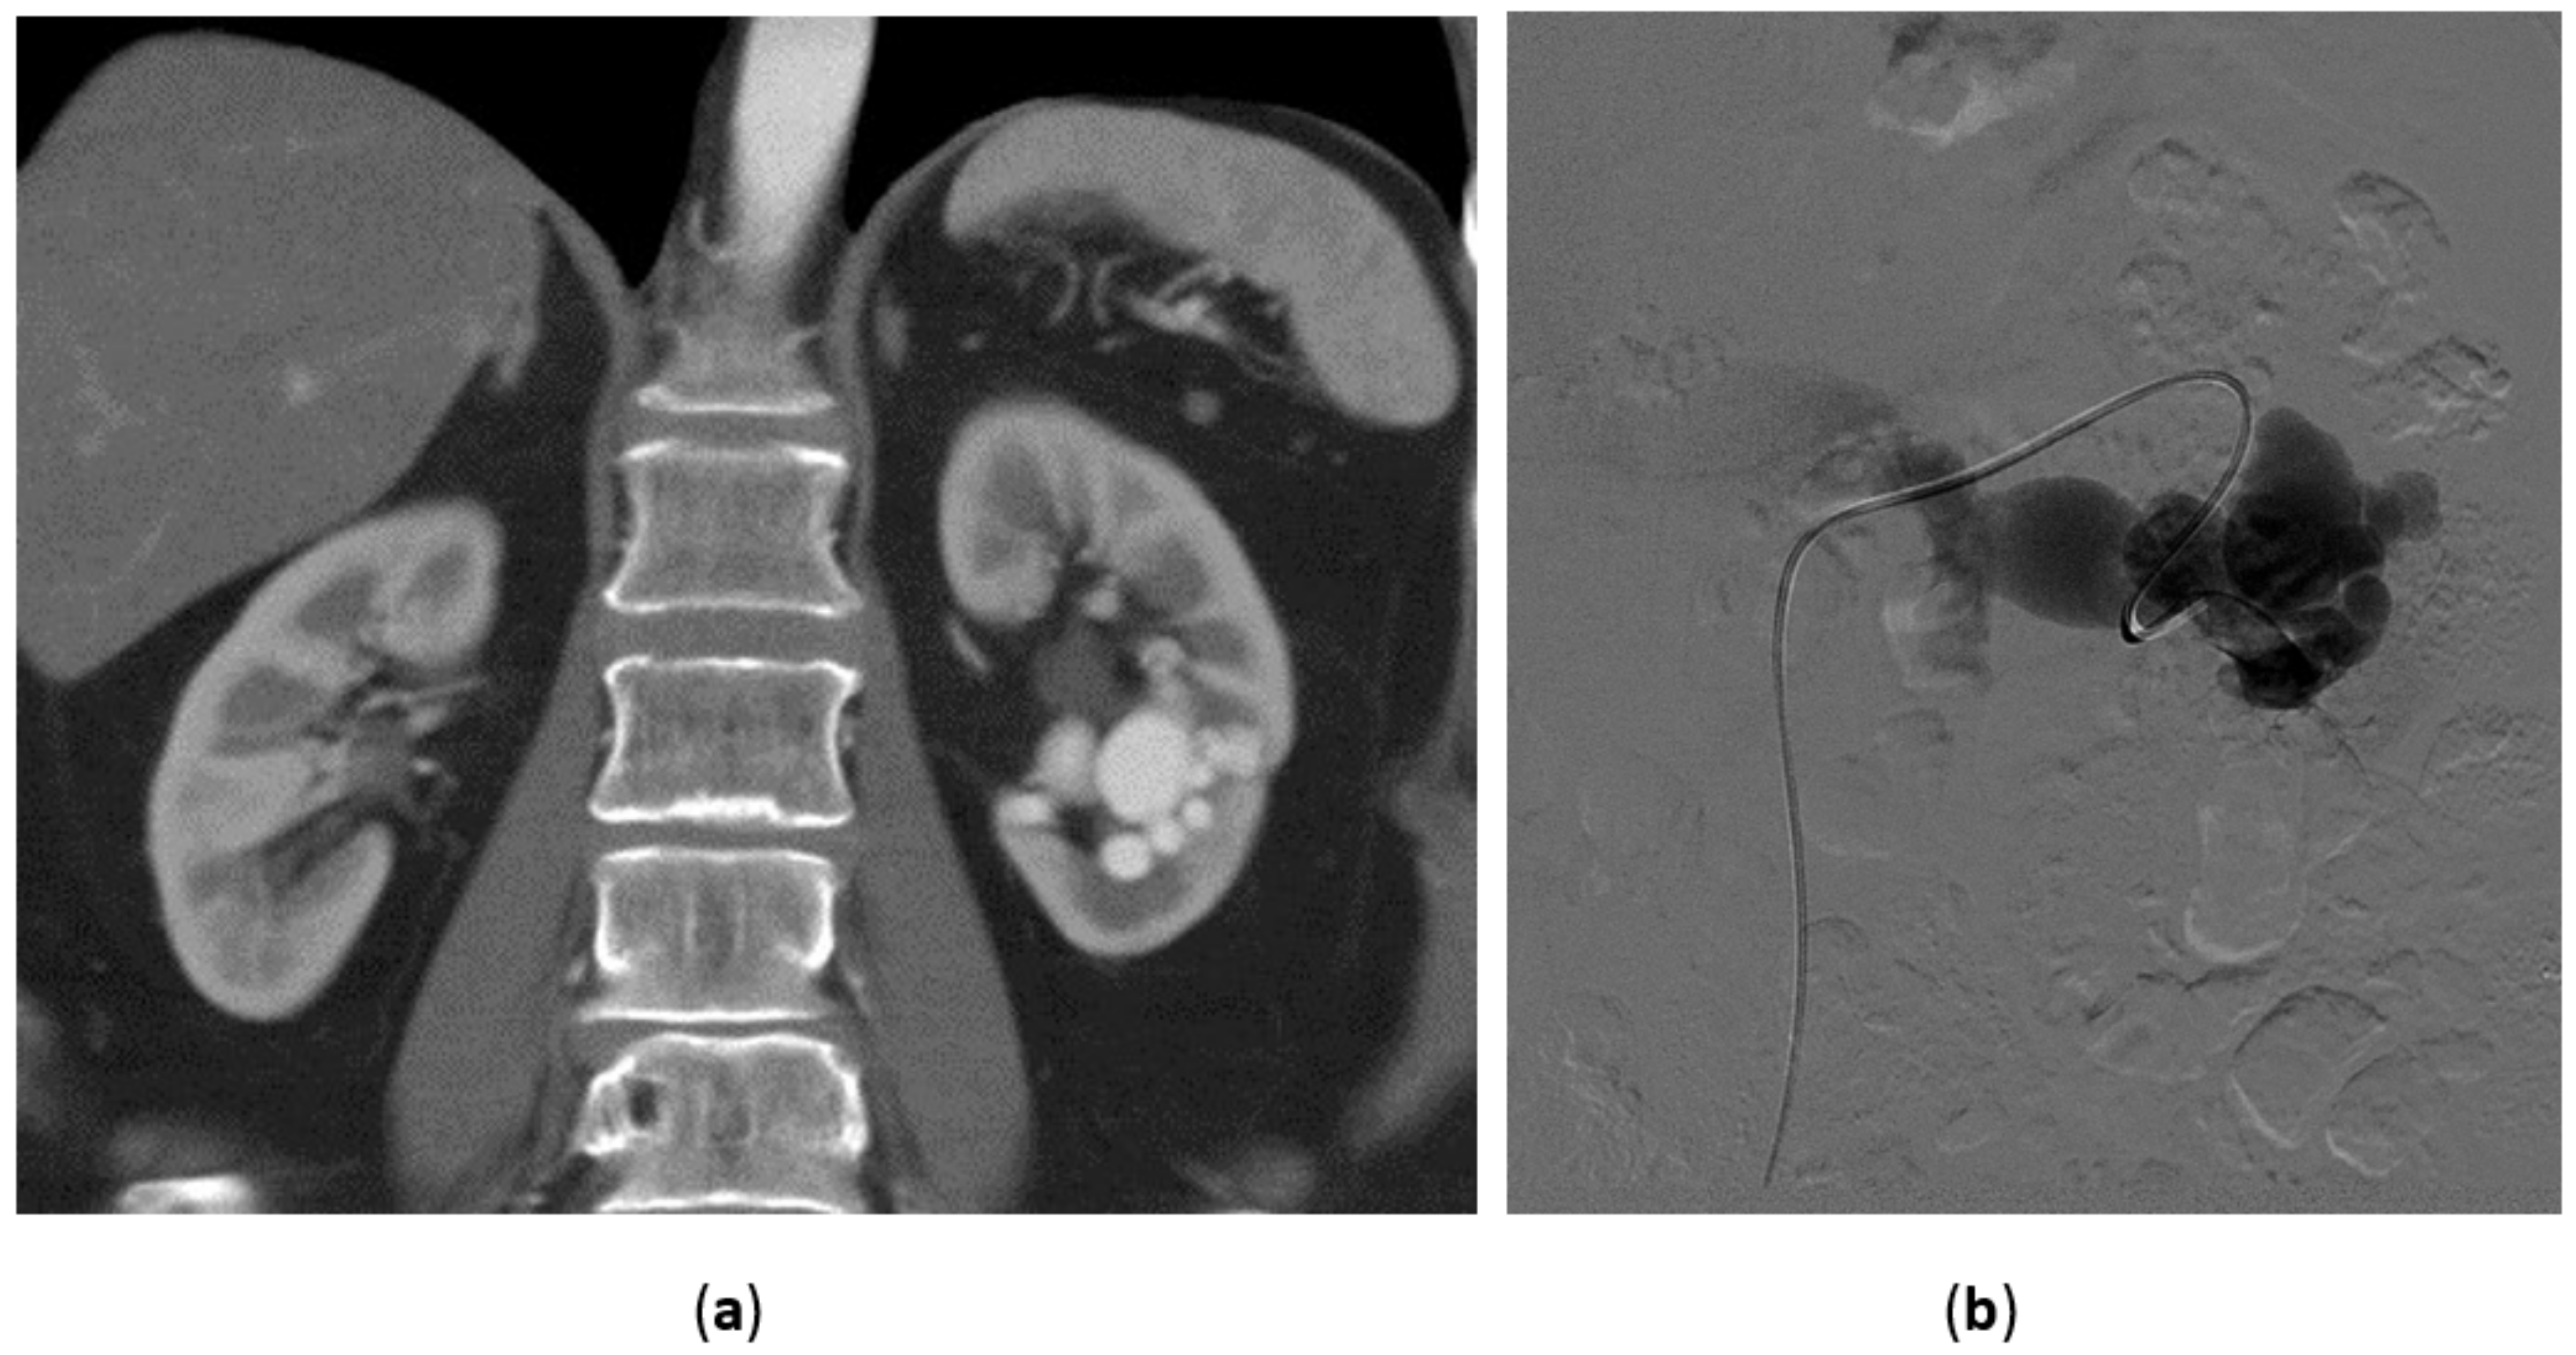

3.2. Renal Artery Pseudoaneurysm (RAP)

3.3. Renal Arterovenous Fistula (AVF)